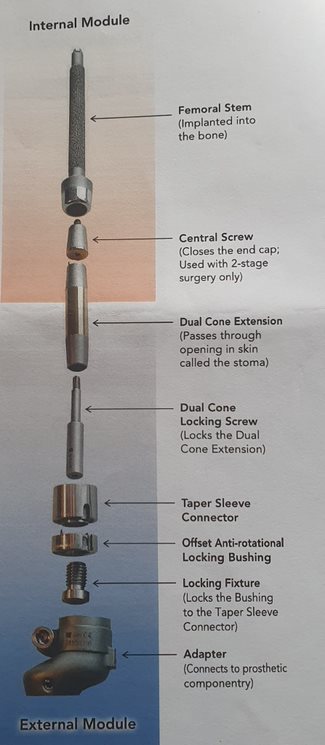

The OGAAP-OPL is made up of several different components that can be divided into an internal (endo) module and an external (exo) module. The endo module, a titanium stem, is directly implanted into the bone. There are a range of implants to meet the needs of varying patients.

The implant surface is highly porous titanium, which allows initial stability and long-term bone integration (in-growth). This technology has been successful in clinical use around the world for more than 30 years in joint replacement surgery. The biocompatibility of the titanium implant allows the bone to grow inside the surface of the prosthesis, which makes the bone-implant structure one solid unit. This is known as osseointegration.

A dual cone extension connects the internal implant to the external prosthesis. This extension has a highly polished smooth surface to minimize soft tissue friction. It is also coated with titanium niobium, which has antibacterial properties. This passes through a small opening in the skin known as the stoma.

Externally, the dual cone extension is fixed to a torque-controlled safety device comprised of a taper sleeve connector and an anti-rotational locking bushing that are held together by a locking fixture. This further connects to an adapter that then connects to the lower prosthetic limb.

There are different adapters available, with different features, yet all are compatible with the various prosthetic componentry in today’s market.

Osseointegration Prosthetic Limb (OPL) Implant for Lower Leg Amputee